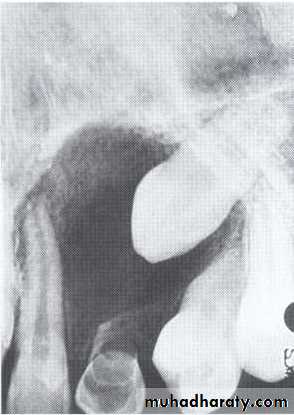

Central giant cell granuloma*A relatively uncommon, non- neoplastic mass in the jaws (intraosseous) producing an expansile radiolucent soap bubble appearance.

*Age; <20 years. Female > Male.

*Teeth are vital, with some root resorption & migration of teeth.

Multilocular appearance, expansion (arrowed) and considerable displacement of the adjacent teeth.

Buccal and lingual expansion (arrowed) and the undulating cortical border.